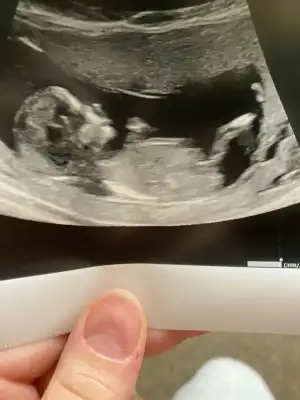

8 hafta ya göre erkek ama siz 11 12 13 hafta nub için paylaşınbize de tahmin yaparmısınız. ikisi de karından usg. ilk resim 9+4 ikincisi 8